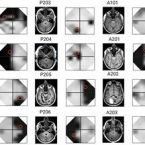

Mapa inicial del déficit del campo visual y de las lesiones.